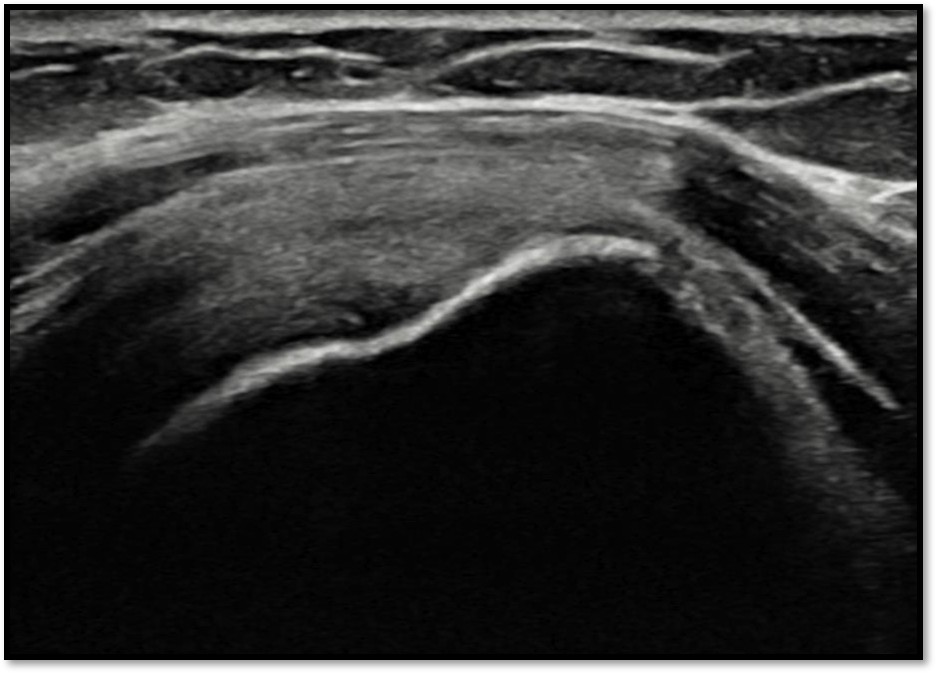

케이스 2: 점액낭면측 파열 → 리제네텐

환자: 38세 여성, 필라테스 강사

진단:

MRI: 극상건 점액낭면측 부분파열 (약 35%)

인대 얇아짐 소견

치료:

리제네텐 콜라겐 패치 적용

재생주사 병행

결과:

16주 후 MRI: 인대 두께 증가 확인

필라테스 강의 복귀